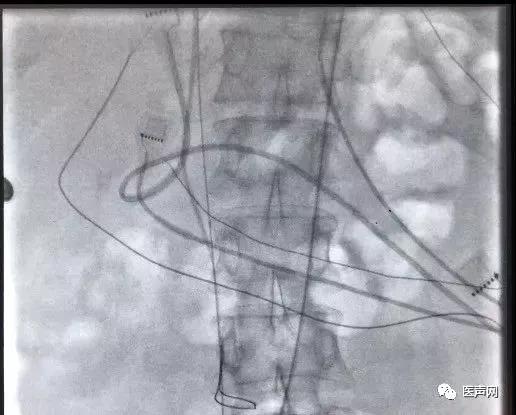

穿刺股动脉并送入造影导管并内置圈套器,降主动脉中圈套长钢丝并抓出体外,在牵拉钢丝过程中使股动脉中的造影导管与房间隔穿刺鞘重叠组套,建立动静脉轨道。

将撤出的导丝调转方向(软头朝前)经该自股动脉造影导管重新送至右心房,下腔静脉。经锁骨下静脉可撕开长鞘送入圈套器,于下腔静脉中抓捕导丝后从锁骨下静脉拉出体外。